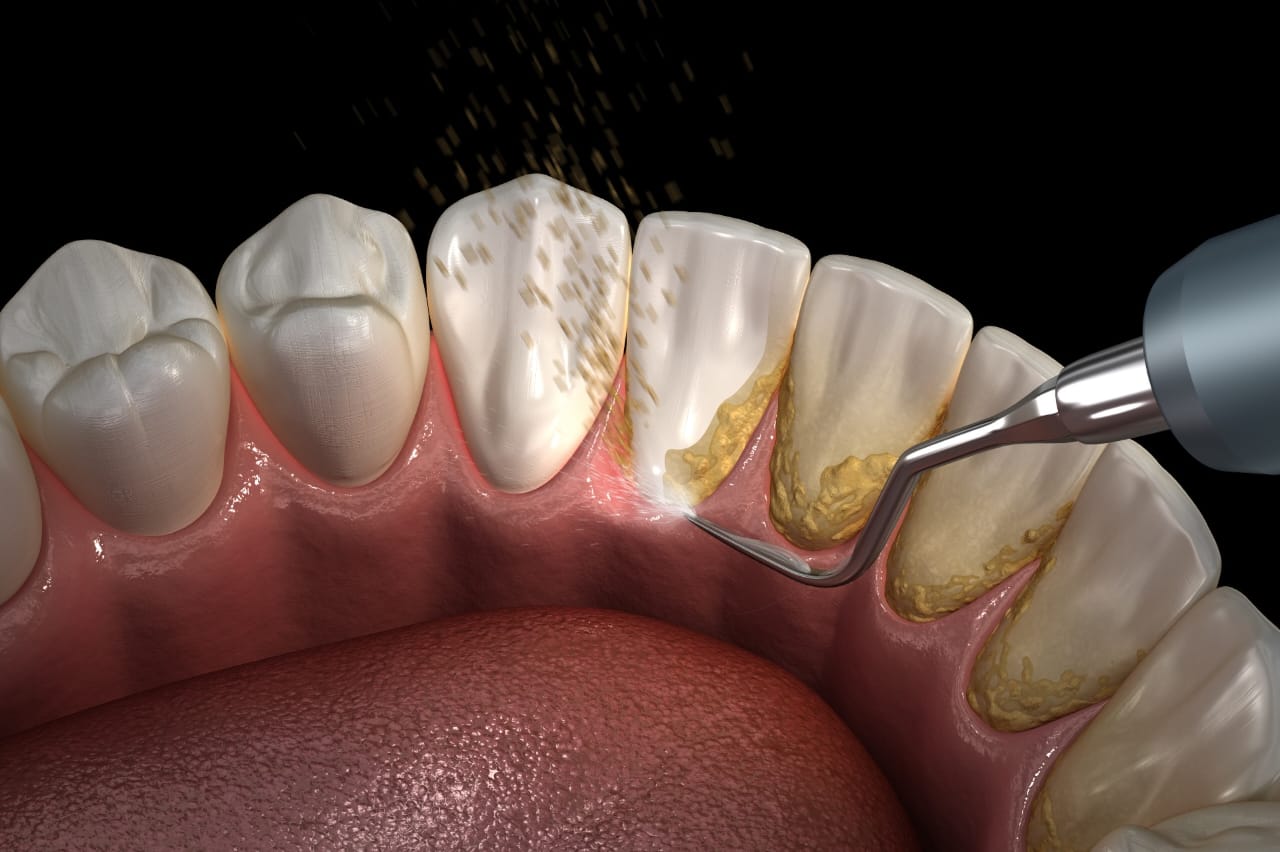

Deep ultrasonic cleaning to remove stubborn tartar and plaque buildup, ensuring healthy gums and fresh breath.